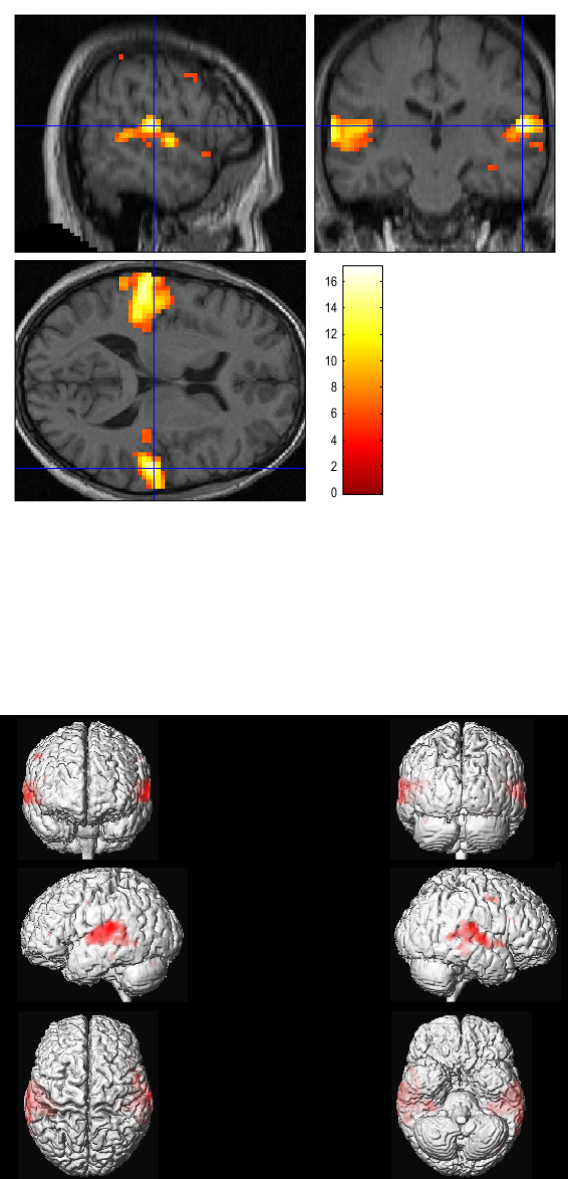

30.4 Inference ..........................................231

30.4.1 Contrast manager ................................235

30.4.2 Masking ......................................235

30.4.3 Thresholds ....................................235

30.4.4 Files ........................................236

30.4.5 Maximum Intensity Projections .........................236

30.4.9 Overlays ......................................240